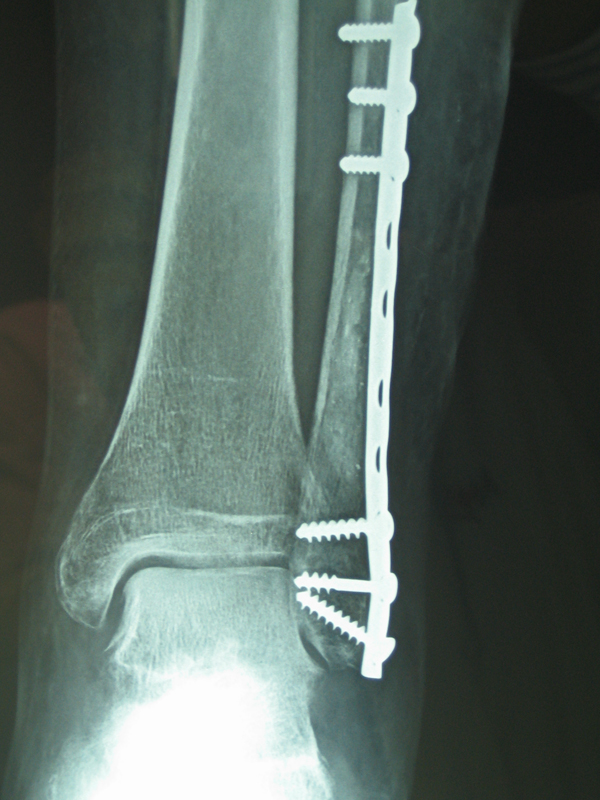

• Οστεολυτική εξεργασία περόνης